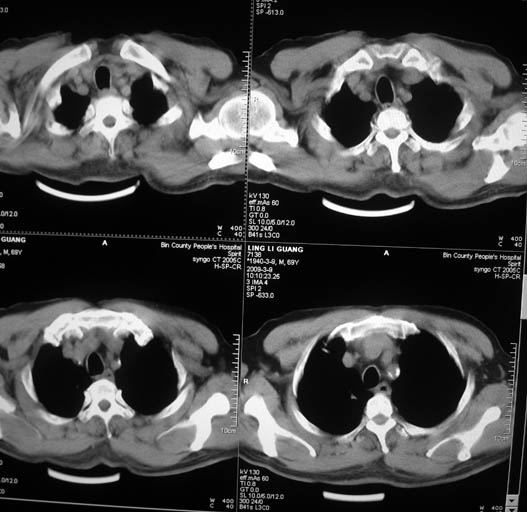

以下是引用随光逐影在2009-3-9 21:36:00的发言:[br]1)两肺上叶尖段结节状病灶,性质待定(不排除肿瘤可能);建议追踪复查。2)右肺中叶内侧段炎症。